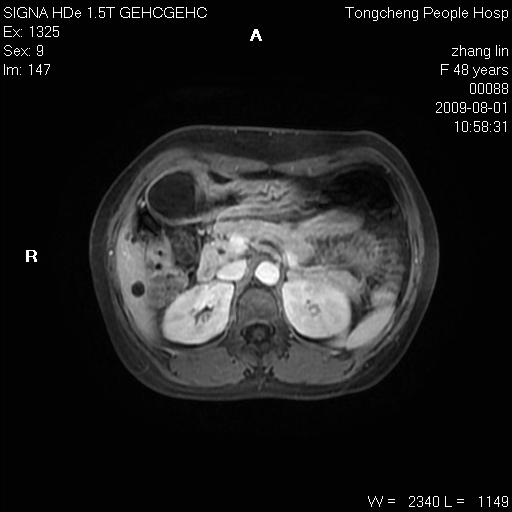

女,48岁。健康体检,彩超发现右肾占位性病变。平素健康。

临床诊断:右肾占位性病变,性质待定(囊肿?肿瘤?)。

上中腹部mr平扫+增强扫描,图像如下:

右肾上极见一类圆形病灶,t1wi呈等信号t2wi呈等高混杂信号,三期增强无强化,边界清---考虑囊肿出血。

同反相位均表现为等信号,病变无强化,考虑含蛋白的囊肿可能,弥散加权相或许有些帮助,